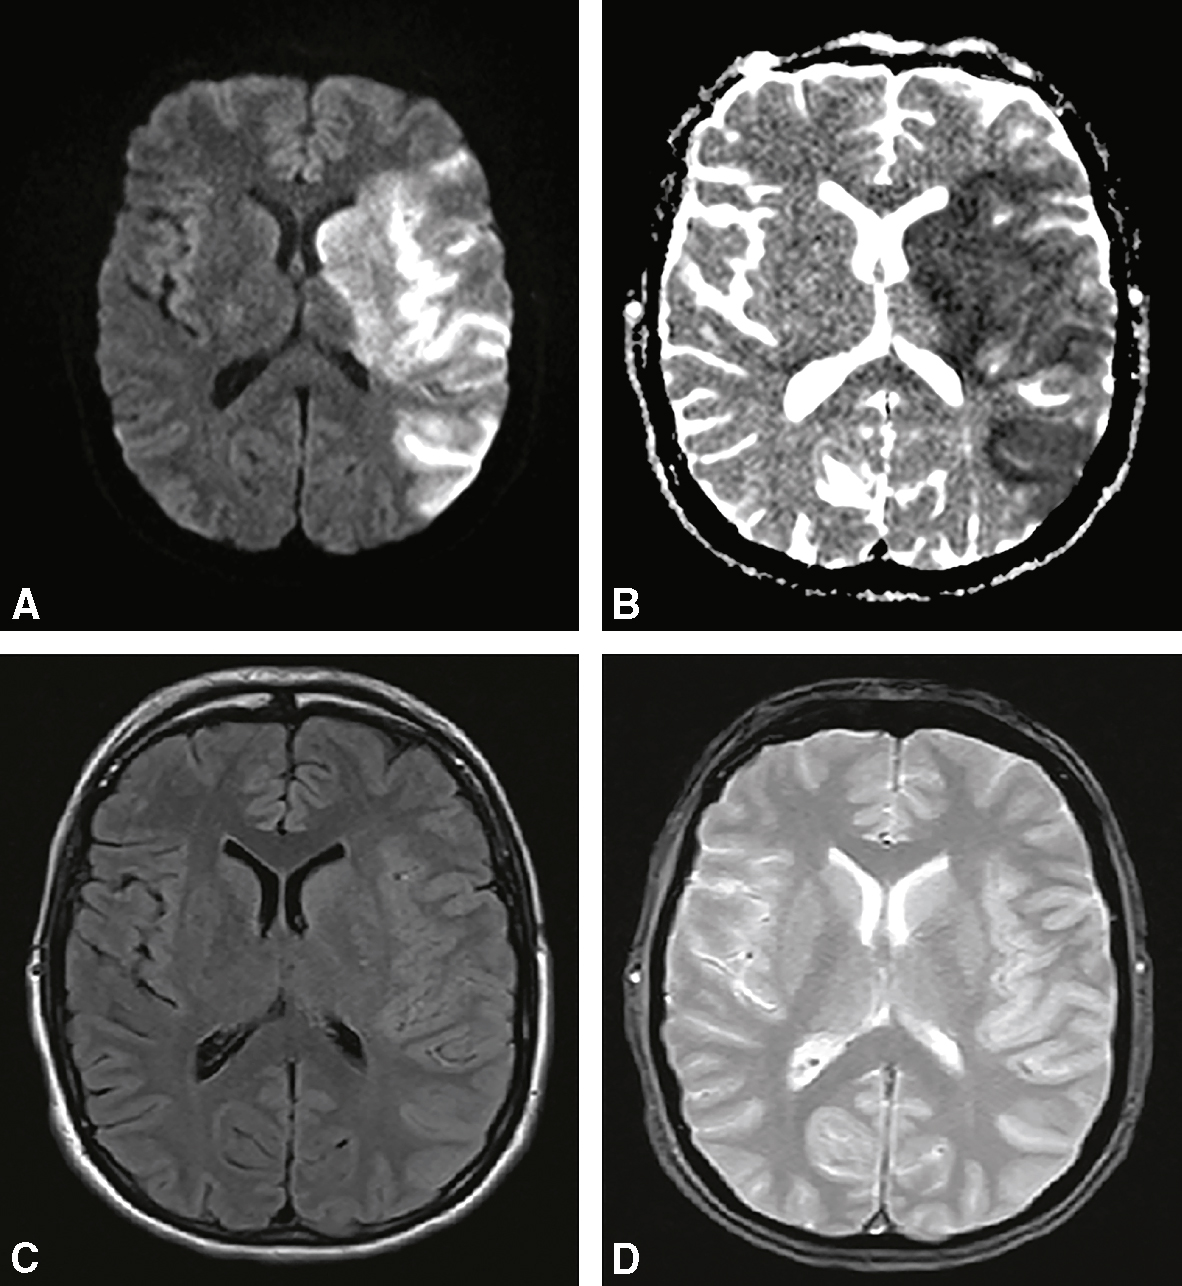

Fig. 28.6 Figure Microangiopathie cérébrale.

A. Infarctus lacunaire récent (IRM séquence de diffusion) hémisphérique droit. B. Infarctus lacunaire ancien (IRM séquence FLAIR). C. Leucoencéphalopathie vasculaire (IRM séquence FLAIR). D. Microbleeds (microsaignement) (IRM séquence T2*).

• – hématomes profonds (noyaux gris) (fig. 28.7A et B);

Fig. 28.7 Figure Hémorragies intracérébrales.

A. Hématome sous-cortical de l’HTA en scanner. B. Hématome sous-cortical de l’HTA en IRM (séquence T2*). C. Hématome lobaire de l’angiopathie amyloïde en scanner. D. Hématome lobaire de l’angiopathie amyloïde en IRM (séquence T2*).

• – hématomes superficiels (ou « lobaires ») (fig. 28.7C et D);

1 Microangiopathie associée à l’HTA chronique

• FigureCause de 50 % des hémorragies intraparenchymateuses.

• • L’hémorragie intraparenchymateuse est secondaire à la rupture des artérioles perforantes, due à l’HTA chronique (fig. 28.7A et B).

• • L’hémorragie intraparenchymateuse associée à l’HTA est typiquement profonde.

• • angiopathie amyloïde (hémorragies intraparenchymateuses lobaires récidivantes + déficit cognitif), cause fréquente chez le sujet âgé (fig. 28.7C et D);